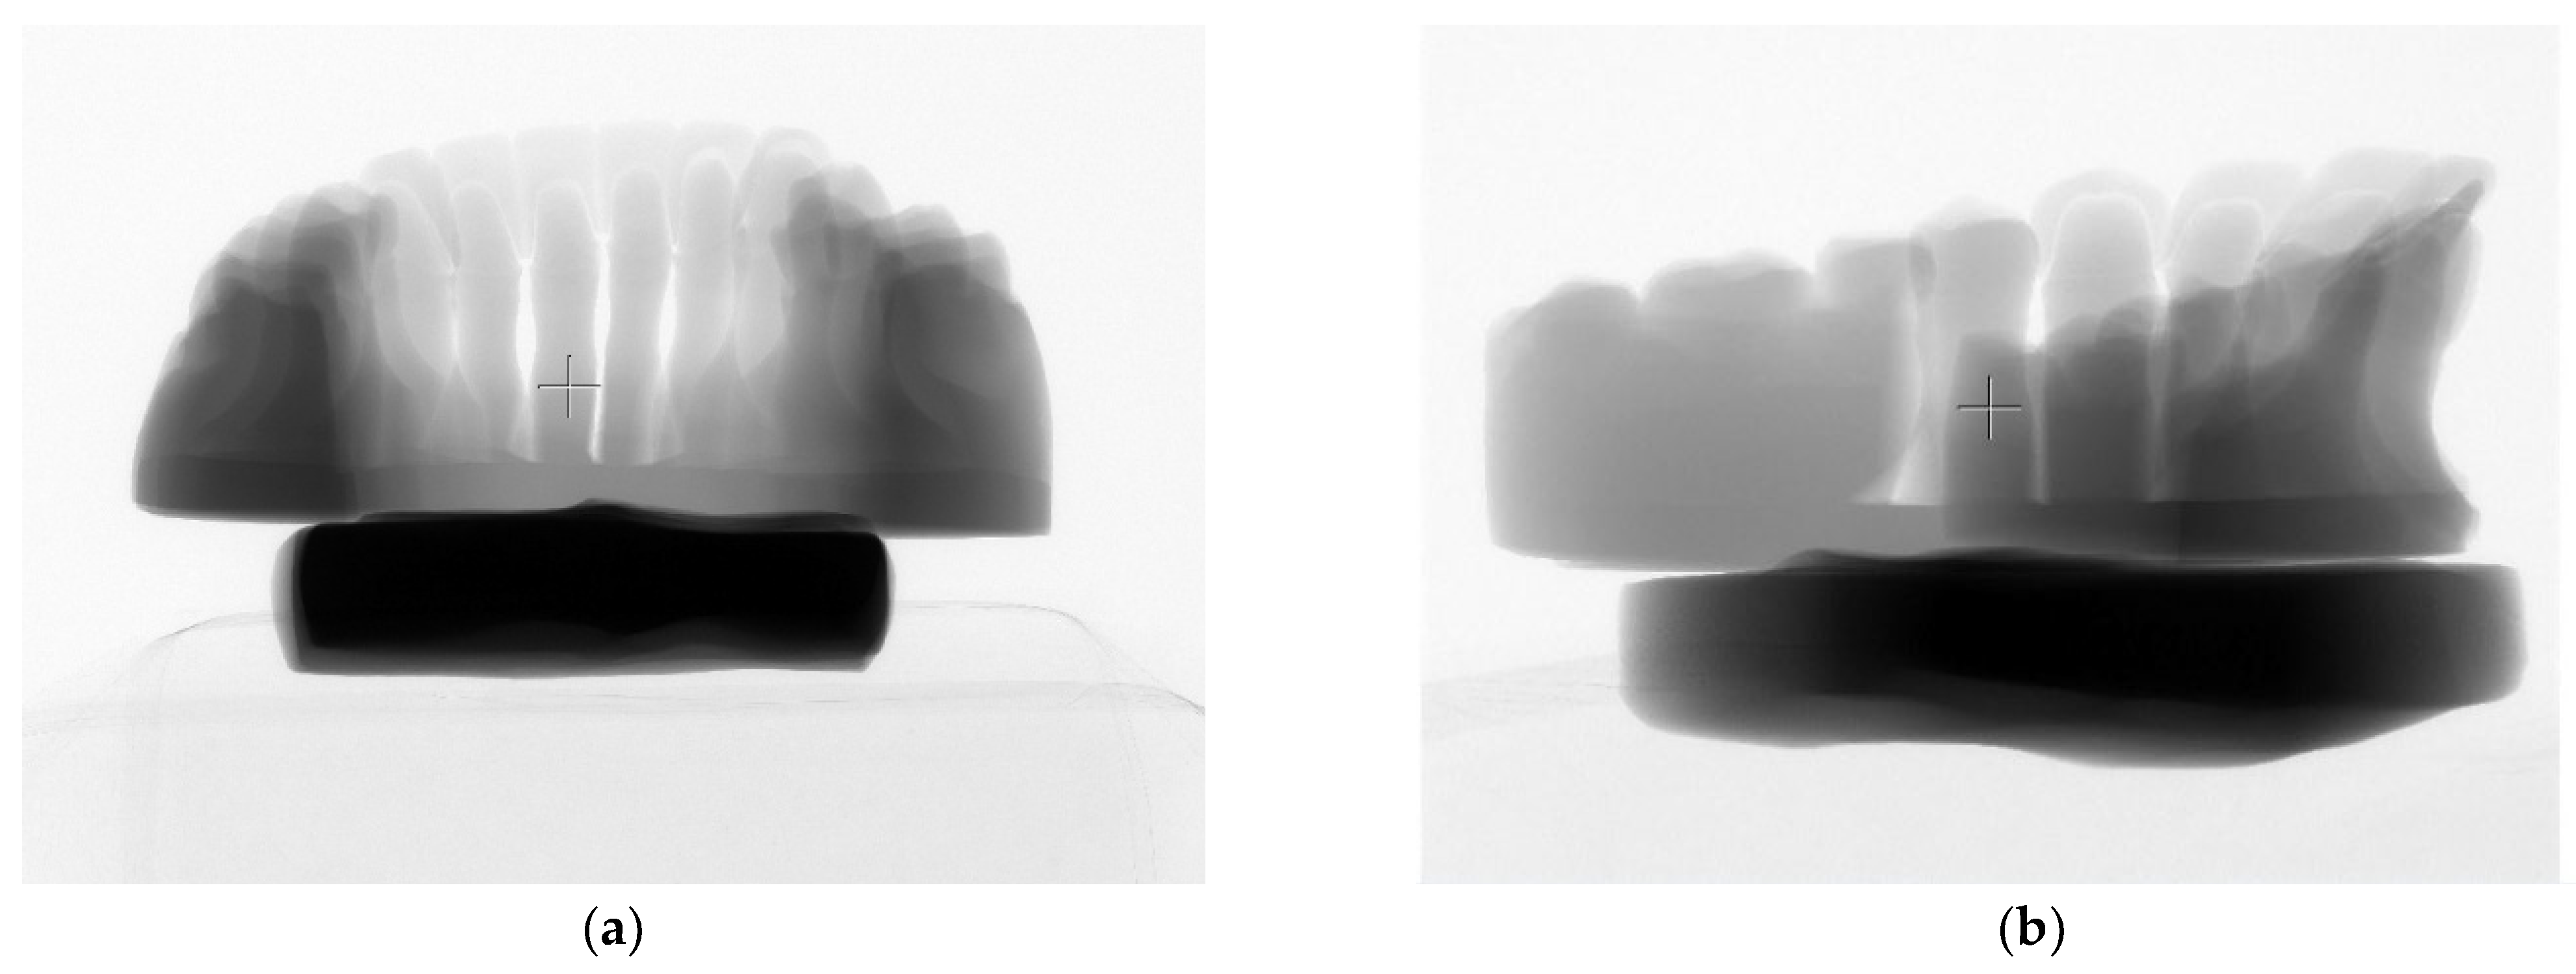

After positioning the samples on the scanning holder, the printed models were scanned together with the preparation guides placed on the teeth. During the analysis, approximately 3000 cross-sectional slices of the models were acquired, followed by the generation of three-dimensional reconstructions (Figure 10a,b).

Figure 10.

X-ray preview of the (a) maxillary and (b) mandibular guides.

After generating the three-dimensional reconstructions, Micro-CT imaging was used solely for the qualitative visualization of the guide–tooth spatial relationships and detection of gross manufacturing defects; no quantitative deviation or accuracy analysis was performed (Figure 11a,b).

Figure 11.

Three-dimensional reconstruction of the (a) maxillary and (b) mandibular preparation guides.